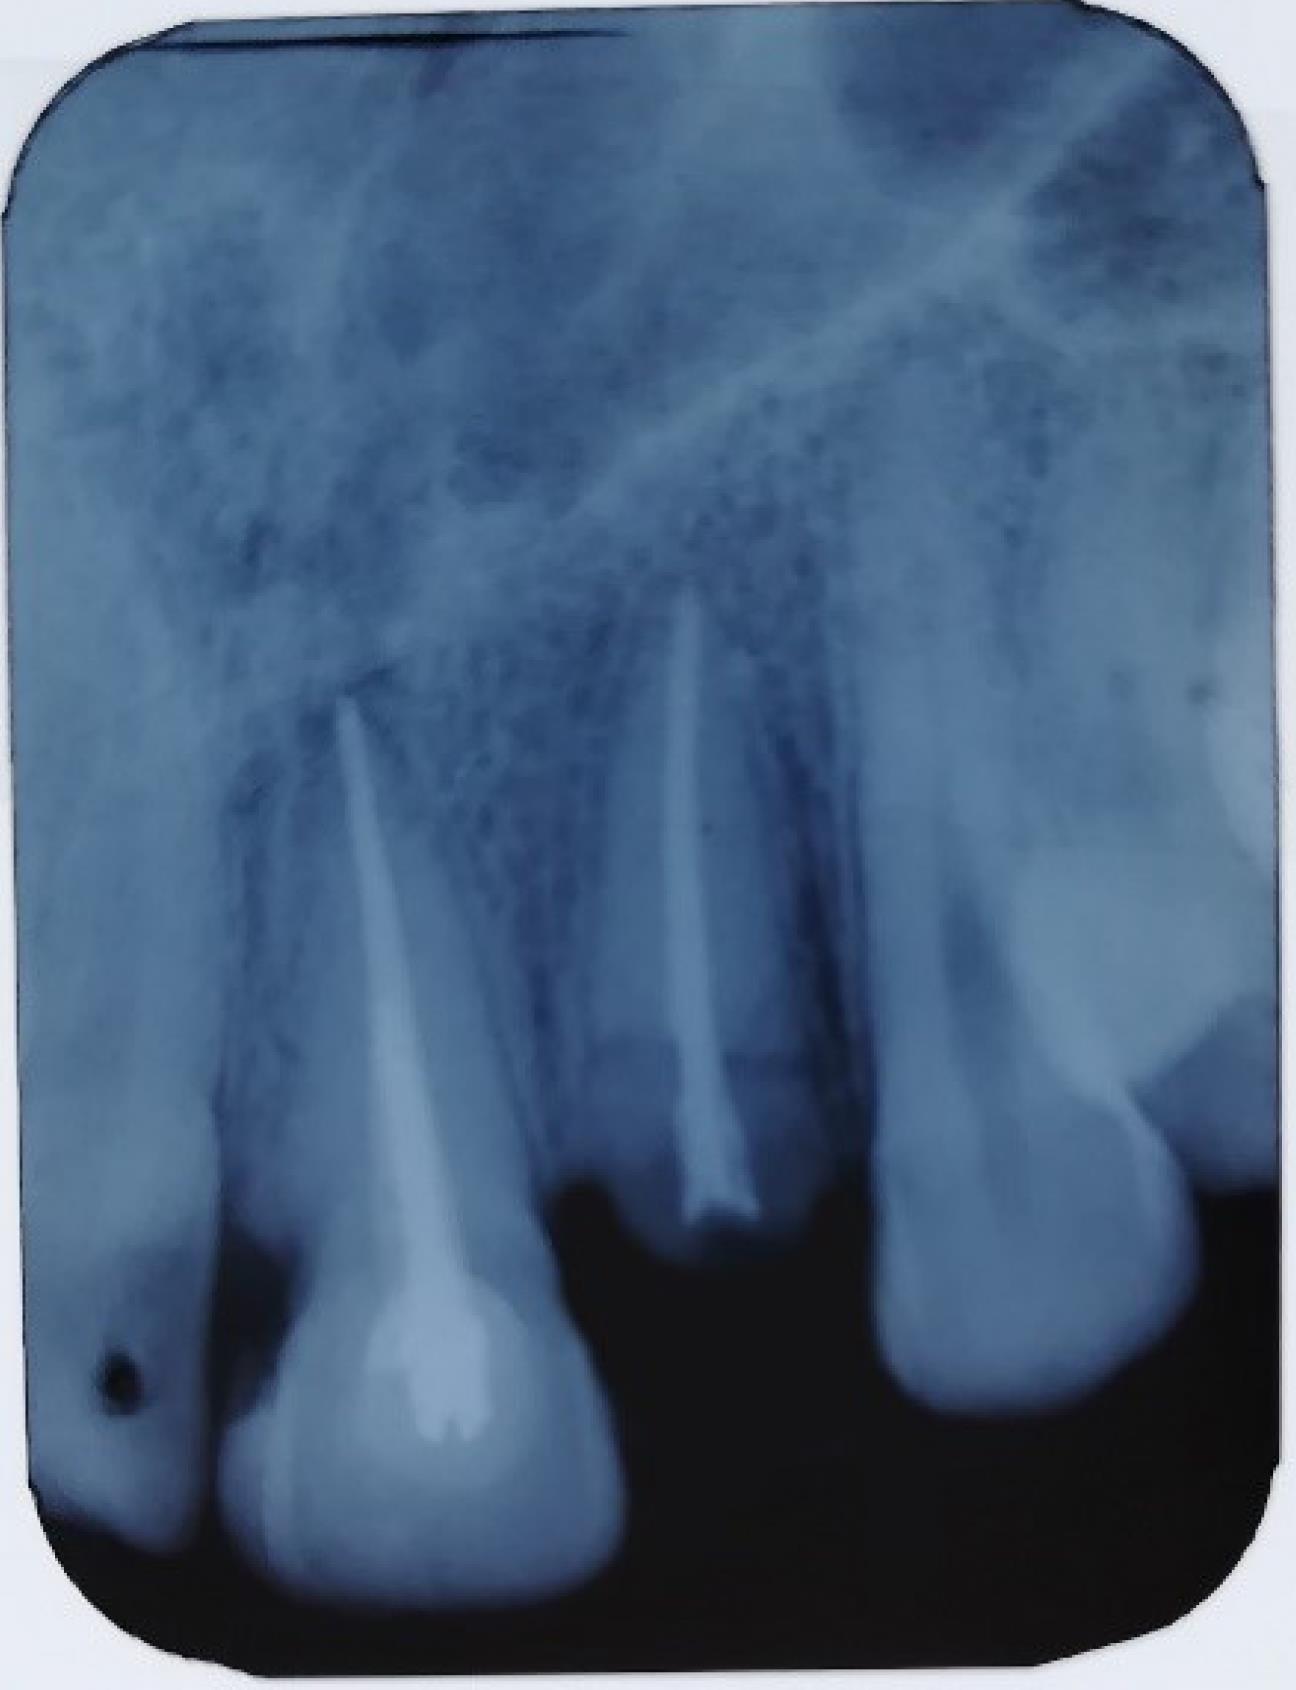

Figure 2.

Preoperative intraoral periapical radiograph